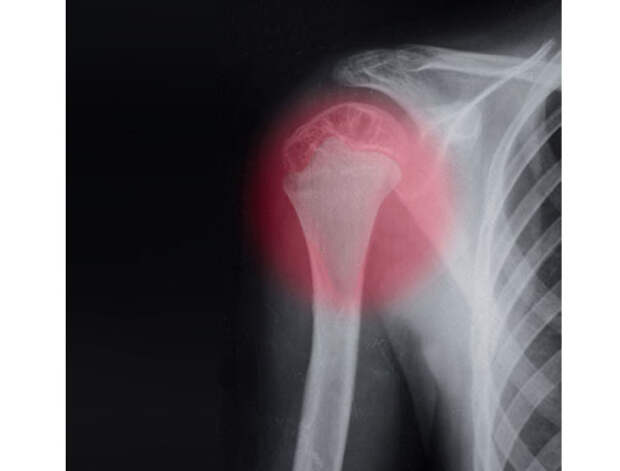

После перелома хирургической шейки правой плечевой кости отмечается ограничение движений руки в области сустава плеча, возникает выраженная боль. Для того чтобы уточнить диагноз, следует произвести рентгенологическую диагностику. Консервативная терапия состоит из вправления костных отломков, обезболивания, обездвиживания конечности (иммобилизации). Если вправление костей (закрытую репозицию) осуществить невозможно, то проводят хирургическое лечение.

Установить диагноз врачу позволяет рентгенологическое исследование сустава. Рентген проводится в горизонтальной (аксиальной) и прямой проекции. Для получения аксиального снимка плечо отводится на 30–40° от туловища. Если отвести плечо на больший угол, возникает высокий риск смещения костных фрагментов. При необходимости проводится компьютерная томография сустава плеча. Довольно тяжело диагностировать вколоченные переломы метафиза (область, в которой диафиз переходит в эпифиз) кости плеча. Это обусловлено тем, что подобная травма не имеет практически никаких клинических симптомов. В процессе обследования важно уметь отличать ушиб или вывих кости от перелома плечевой шейки.